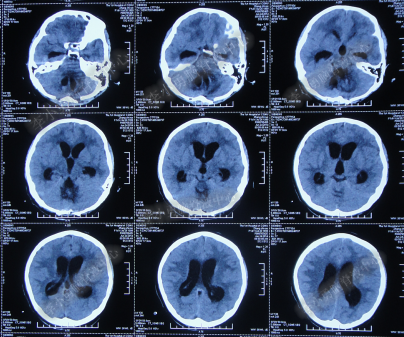

患者因恶心、呕吐伴头痛头晕,自行服药后无法自行缓解,于2014年5月29日就诊位于重庆的著名的三甲肿瘤医院,查全脑CTA和CT后诊断为“小脑蚓部占位伴幕上脑积水”(图-1、图-2)。

图-1:2014年5月29日全脑CTA

图-2:2014年5月29日头部CT